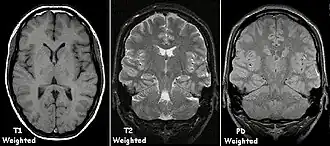

Examples of T1-weighted, T2-weighted and PD-weighted MRI scans

To generate an observable image using MRI, the target is placed in a powerful magnetic field, such as that of an MRI machine. This causes the axes of the hydrogen protons inside the target, which are usually randomly aligned according to equilibrium, to be lined up in the same direction, creating a magnetic vector oriented along the magnet's axis. This orientation also allows the hydrogen protons' spin, or frequency of rotation, to be measured. The alignment is then disrupted using radiofrequency (RF) pulses (RF being a type of non-ionizing electromagnetic radiation).[45] When the magnetic field is removed, the hydrogen protons return to their equilibrium states in a process known as relaxation, and in doing so they emit RF energy.[46] Different tissues relax at different rates, which allows scientists to use specific RF pulse sequences to emphasize particular tissues or abnormalities.

After a period of time following the RF pulse, the RF energy signals emitted by the protons are measured to obtain frequency information from each location in the imaged plane. Then Fourier transformation is used to convert this frequency information into intensity levels, which are displayed as shades of grey in the generated image.

A FLAIR-weighted axial MRI section showing multiple white matter lesions in the cerebral hemispheres

In general, two aspects of the relaxation process are measured: the time taken for the magnetic vector to return to its resting state (also known as T1 or spin–lattice relaxation), and the time taken for the axial spin of the hydrogen protons to return to its resting state (also known as T2 or spin–spin relaxation).[47] To create a T1-weighted image, the MR signal is measured by changing the amount of time between RF pulses (also known as the time to repeat, or TR). To create a T2-weighted image, the MR signal is measured by changing the amount of time between delivering the RF pulse and receiving the RF energy signals from the hydrogen protons (also known as the time to echo, or TE). The dominant signal intensities of T1 image weighting are fluid (black due to low intensity), muscle (grey due to intermediate signal intensity), and fat (white due to high signal intensity). Fat suppression is applied to many T1 weighted sequences to suppress the brightness of the signal created by it. The dominant signal intensities of T2 image weighting are fluid (white), muscle (grey), and fat (white). T2 signals are also often emphasized or suppressed depending on what the goal of the imaging is; notable examples include fat suppression, fluid attenuation, and susceptibility weighting.

Also of note are proton density (PD) weighted images, which are generated using a long TR and a short TE. PD is useful for differentiating between fluid, hyaline cartilage and fibrocartilage, which makes it ideal for imaging joints. Outside of joint imaging it has largely been replaced by fluid attenuated inversion recovery (FLAIR), an inversion recovery sequence that removes the signal from cerebrospinal fluid.[48]